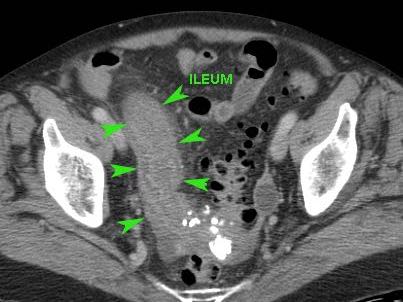

Ở bệnh nhân này, siêu âm cho thấy lượng lớn mô mỡ viêm (*) và hồi tràng dày thành, biểu hiện quá trình bao bọc thành công tình trạng thủng (sắp xảy ra) của ruột thừa (mũi tên).

Lưu ý sỏi phân vôi hóa (mũi tên trên CT) trong ruột thừa ở mức cao hơn.